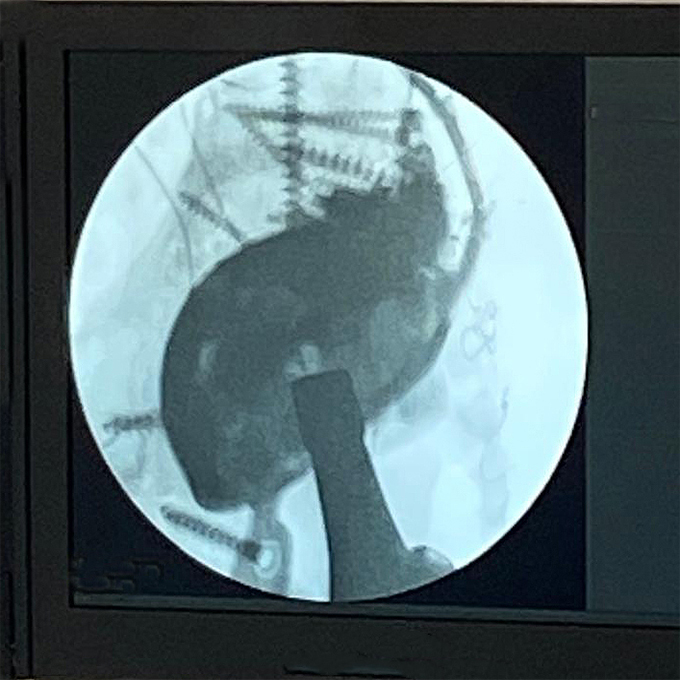

Intraoperative fluoroscopic assessment during definitive reconstruction.

Postoperative X-ray showing integrated augment–cage construct with stable fixation, allowing early full weight-bearing.

The extreme malleable flanges allowed the cranial fixation.

Off-the-shelf MobileLink PPR using a Dual Mobility Insert, combined with a TrabecuLink Augment.

At 18 months follow-up, the patient remains asymptomatic. He ambulates without walking aids and demonstrates active hip flexion of 90 degrees. There are no clinical or laboratory signs of recurrent infection.

This case highlights the dual challenge inherent to chronic multidrug-resistant PJI in the presence of severe acetabular bone loss. Biological eradication of infection required aggressive debridement and high-dose local antibiotic delivery. Mechanical reconstruction required understanding the biomechanics of the defect rather than relying solely on classification.

The absence of the posterior wall created anteroposterior instability that could not be resolved by cranial augmentation alone. By mechanically linking a trabecular titanium augment to a PPR cage, structural logic was restored. Stability was achieved not through implant complexity but through coherent construct integration. In multiply revised hips, dual mobility articulation adds an additional layer of safety by reducing dislocation risk in compromised soft tissue environments.

Ultimately, successful salvage revision depends on addressing infection control and structural reconstruction simultaneously. When both are conceptually aligned, even severely compromised hips can regain function and durability.